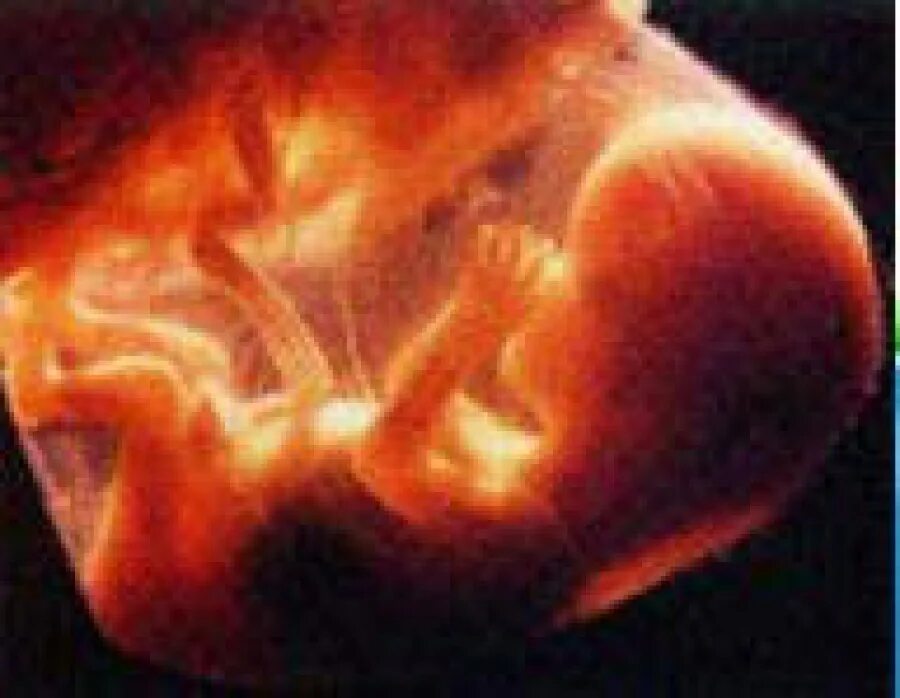

Как выглядит 16 неделя беременности фото